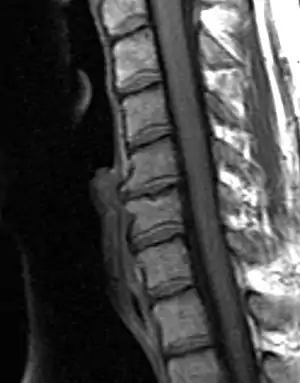

Degenerated disc between C5 and C6 (vertebra at the top of the picture is C2), with osteophytes anteriorly (to the left) on the lower portion of the C5 and upper portion of the C6 vertebral body. | |